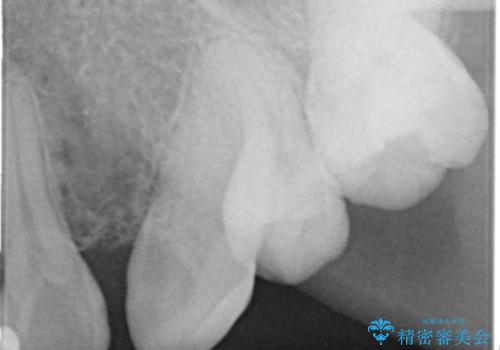

精査したところ、右上の側切歯(右上2)は神経が死んで変色しており、左上の側切歯と犬歯の間に2mm程度の隙間を認めました。

矯正せずに早く治したいという強いご希望により、セラミッククラウンによる補綴治療(上顎両側2の2本)を行いました。